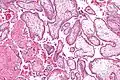

Micrograph showing chorionic villi. Very high magnification. H&E stain.